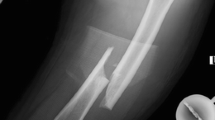

The patient was an 83-year-old Japanese woman with osteoporosis, treated with Risedronate and Alfacalcidol for the previous 5 years. She started to have left lateral thigh pain and claudication following a low-energy fall 4 months prior to admission. Radiographs revealed thickening of the lateral cortex and a transverse radiolucent fracture line in the diaphysis (Fig. 3-1, 4). In 2007 she had bilateral knee arthroplasty. In addition, the contralateral thigh showed significant femoral bowing. The fracture fulfilled the ASBMR task force revised criteria for atypical femoral fractures [6]. By MRI, there was a high intensity signal 1 cm long on the lateral cortex on a T2WI image (Fig. 3-2,3). The patient had normal levels of bone resorption and formation markers except for low 25(OH) Vitamin D. She suffered from CKD, and a DXA showed low BMD of the hip and lumbar spine (Table 1).

Preoperative X-ray, MRI, and postoperative X-ray. 1 Preoperative X-ray of the left femur, with lateral bowing and hypertrophy of the lateral cortex on both periosteal and endocortical surfaces of the midshaft. 2 Preoperative MRI of the left femur, showing high intensity area in the bone marrow adjacent to the mid-lateral cortex (yellow arrow). 3 Preoperative MRI of the left femur, showing high intensity area in the intracortical region of the mid-lateral cortex (upper end: yellow arrow; lower end: red arrow). 4 Preoperative X-ray of the left femur. An enlarged image of the midshaft, indicating the hypertrophy of both periosteal (white arrow) and endocortical (yellow arrow) surfaces. 5 Postoperative X-ray of the left femur: lateral bowing was corrected and fixed with intramedullary rodding and plate fixation